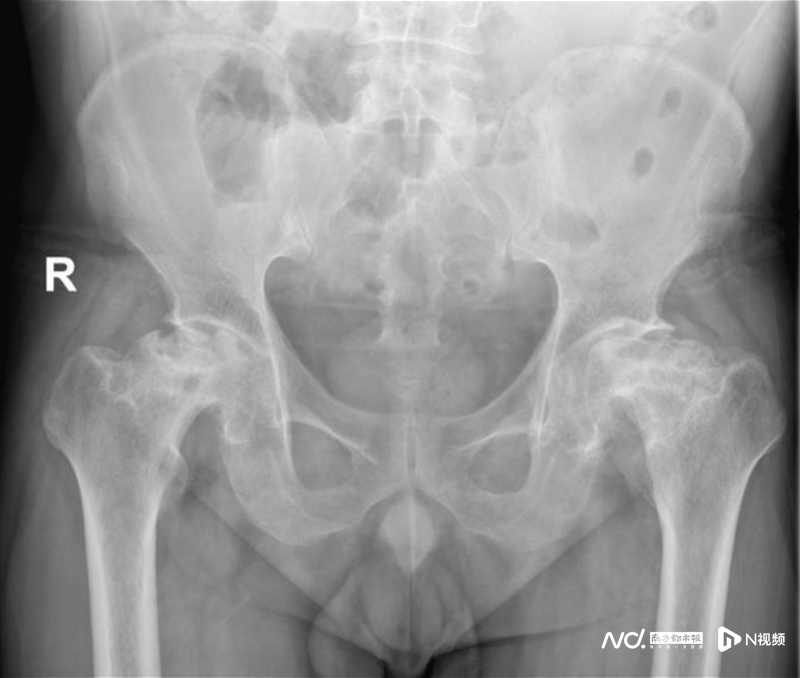

前不久,因病情加重致行走困難,影響日常生活,他才來到廣州和平骨科醫(yī)院骨科就診。經(jīng)過相關(guān)檢查后,確診為“雙側(cè)股骨頭缺血性壞死、雙髖關(guān)節(jié)退變、雙側(cè)髖關(guān)節(jié)半脫位”,需要進(jìn)行雙側(cè)人工全髖關(guān)節(jié)置換。

術(shù)前影像檢查,患者的雙側(cè)股骨頭均已嚴(yán)重壞死。

不得不接受雙側(cè)人工全髖關(guān)節(jié)置換。